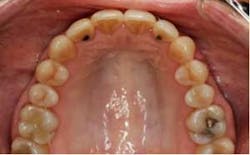

SFOT was used with a high-tech clear aligner to address hard- and soft-tissue deficiencies and severe maxillary and mandibular arch constriction.

SFOT surgery was performed in the maxillary and mandibular arches with deep buccal corticotomies. Particulate, demineralized, freeze-dried bone allograft and acellular dermal matrix were used to augment the ridges.

Total treatment time: 6 months. Patient declined recommended further clear aligner refinement and fine-tuning periodontal plastic surgery.